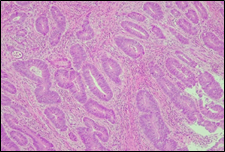

The present study concluded that, out of the total 77 patients with colorectal neoplasia, 17 (22.1%) had a high degree of differentiation (G1), 51 (66.2%) had a moderate degree of differentiation (G2), and 9 (11.7%) had a low degree of differentiation (G3). Figure 3 illustrates the different morphopathological forms of colorectal neoplasia observed in the patients included in the study.

A | B |

C | |

Fig. 3 Morphopathological forms of colorectal tumors (degree of differentiation) A – conventional highly differentiated colonic adenocarcinoma (G1) (HE stain, ×200) B – moderately differentiated (G2) conventional colonic adenocarcinoma (HE stain, ×200) C – conventional poorly differentiated colonic adenocarcinoma (G3) (HE stain, ×200) | |

For patients with colorectal neoplasm, investigating the correlation between the macroscopic aspect of the tumor formation visualized endoscopically and the degree of differentiation described histologically, it was found that there is no statistically significant relationship (p > 0.05), which is above the threshold accepted for demonstrating a significant statistical correlation. It is known that most colorectal adenocarcinomas develop at the site of precursor lesions, such as adenomas and dysplasia. Residual adenoma is a phenomenon commonly found in colorectal adenocarcinomas. Typical adenomas are subclassified into tubular, tubulovillous, and villous types based on their architectural and histological features. Tubular adenomas consist of dysplastic glands that resemble cryptic intestinal glands and contain less than 25% villous component. Villous adenomas are composed of more than 75% villous components, which appear as fibrovascular rods covered by dysplastic epithelium. Tubulovillous adenomas represent intermediate lesions with a villous component ranging from 25% to 75%.